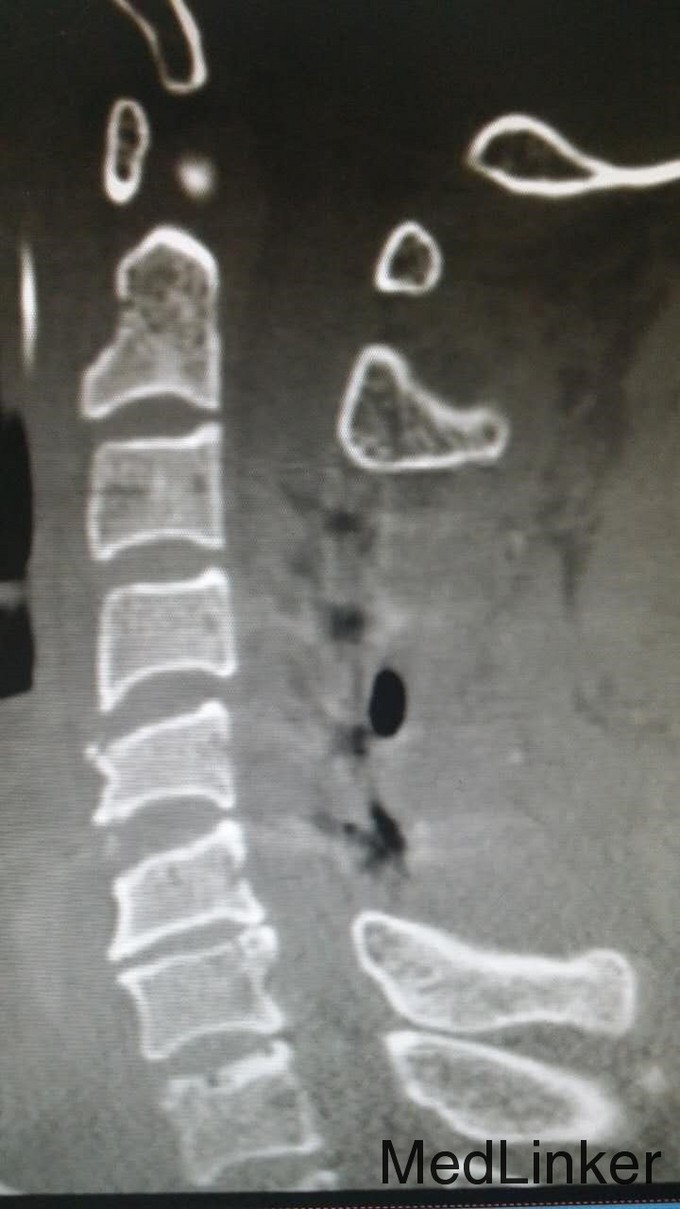

主诉:头颈部重物咂伤5小时伴四肢瘫 病史:入院5小时前,头颈部被门板砸伤,伤后全身疼痛,伴四肢瘫。

查体:T4平面以下痛觉消失,四肢肌力0级。双侧病理征阳性。 辅检:全身CT示:C4左侧椎扳、侧块、C5-6左侧横突多发骨折,C5椎体压缩骨折,C4椎体滑脱,颅内未见明显血肿,胸腹盆末见明显外伤行病变。头颅MRI示:C3-6水平颈髓出血伴水肿。

诊断:1.C3-6水平颈髓损伤出血伴水肿,2.C4左侧椎扳、侧块、C5-6左侧横突多发骨折,3.C5椎体压缩骨折,4.C4椎体滑脱(Ⅰ度) 治疗:伤后5天,予行C3-6椎板切除、椎管减压,侧块固定融合术